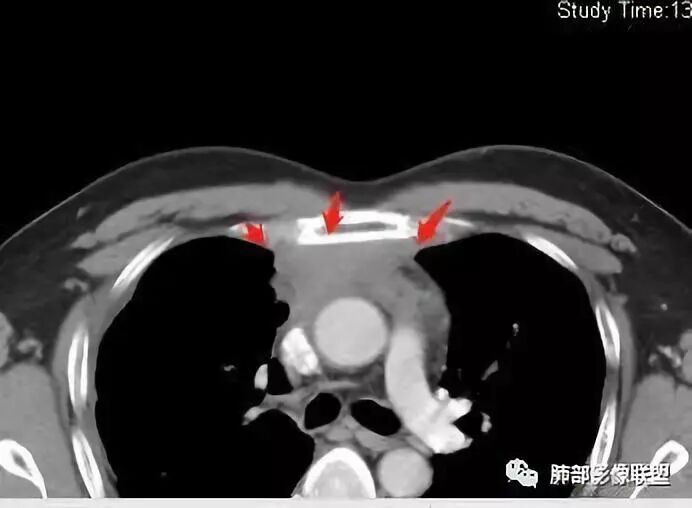

Coke with ice:囊性部分考虑包裹性积液?南边:不是积液;有间隔;张力高;而且位置有些特殊

大家仔细看看积液中的游离气体;

不是支气管,是积气;是穿刺进去的;

囊内密度不一致

我认为囊张力高,积液中的气体均在周围,外侧、下方,囊内有间隔:各腔密度不一致;提示:囊腔属于前纵隔,不是包裹性积液;现在的问题:囊腔与内侧的病灶是否是一体的